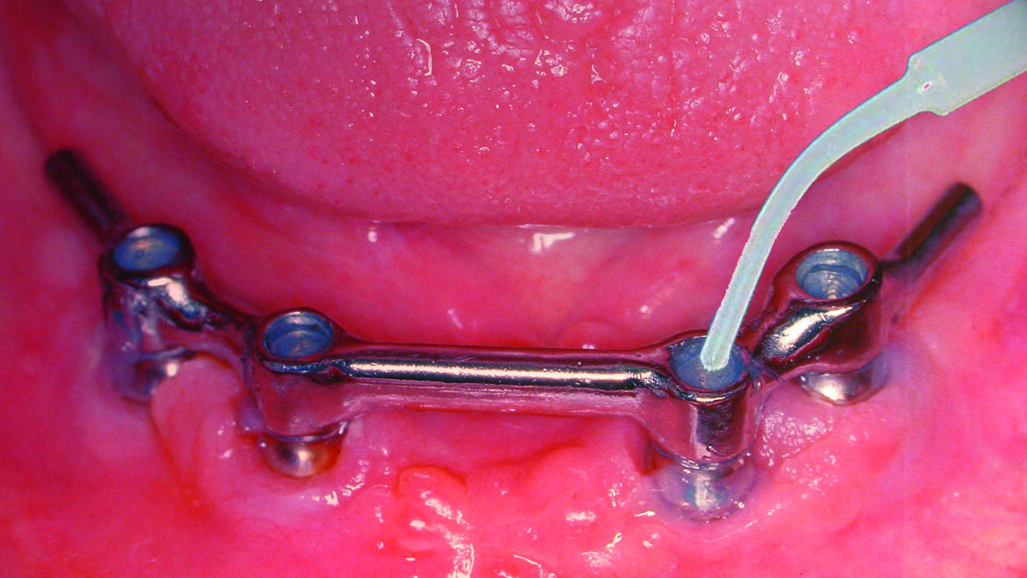

Fig. 2: Recesses underneath a mandibular prosthesis supported by an implant bar.

Fig. 4: Filling of an implant bar construction in the mandible with GapSeal.

GapSeal is supplied in sterile blister packs containing ten ampoules of 0.06 ml each and an applicator, ensuring sterility even for surgery (Fig. 3). The applicator can be resterilised for reuse. Hollow spaces should be sealed as soon as possible—preferably at the time of restoration. After inserting the GapSeal ampoule into the applicator and removing the cap, the clinician applies GapSeal directly by simply turning the wheel. The space is filled with a surplus of material so that there are no air pockets. The ampoules are designed for single use. In the situation that the hollow spaces cannot be loaded with the sealing material until later, it is recommended to clean them thoroughly beforehand with hydrogen peroxide and alcohol. In the case of a prosthesis with retaining screws, the dentist should re-apply GapSeal at recall appointments (Fig. 4).